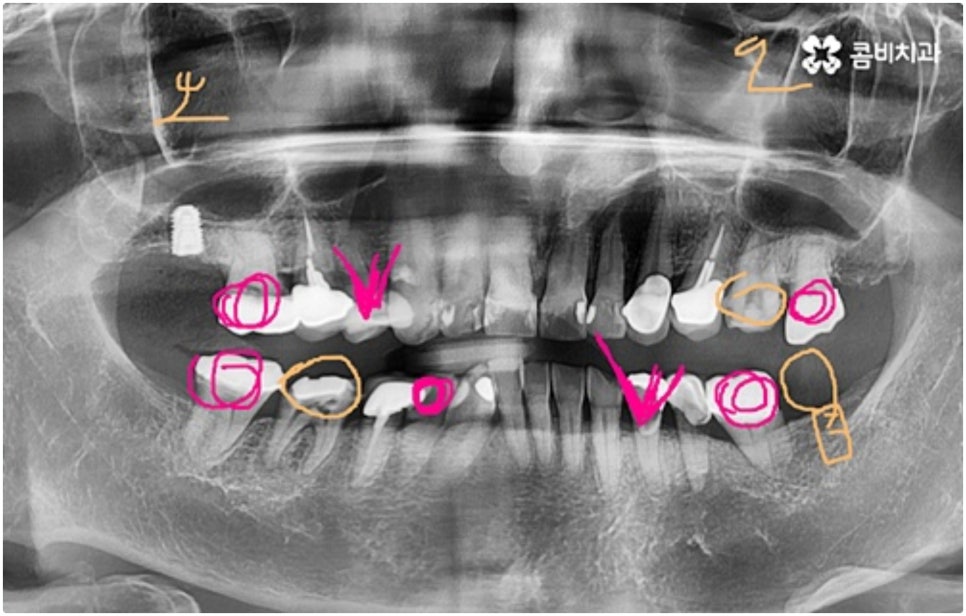

모든 치아가 위치와 모양이 제각각 다른데 특히 어금니는 구강 내 깊은 곳에 있고 주름진 저작면을 가지고 있기 때문에 관리할 때 더욱 주의할 필요가 있습니다. 꼼꼼하게 칫솔질을 해준다고 해도 음식물 찌꺼기가 남게 될 가능성이 높아 충치나 치주염 등 구강 질환이 빈번하게 발생할 수 있기 때문인데요, 이때 빠른 발견으로 초기 대처를 해주지 못하면 내부 신경까지 손상이 깊어져 치아를 발치하고 어금니임플란트 시술을 받아야 할 상황까지 발생할 수 있어요.

구강 질환 때문이 아니더라도 저작 기능의 핵심적인 역할을 담당하고 있어서 외부 충격 (실수로 딱딱한 것을 씹는 일 등) 에 노출될 위험도 큰데요, 만약 부러지고 금이 갈 때 뿌리까지 갈라졌다면 해당 어금니는 살릴 수 없고 인공 치아로 대체해야 할 거예요.

임플란트 시술이 환자분들의 잇몸뼈에 직접 고정을 시키는 방법인 만큼 개개인의 치주 상태, 구강 내부 구조 등을 면밀하게 살펴보고 치료 계획을 세워야 하며 그 밖에도 치아가 빠진 지 얼마의 시간이 흘렀는지, 장기적으로 복용 중인 약이 있는지 등 영향을 줄 수 있는 모든 관련 상황을 종합적으로 고려하여 환자분들에게 딱 맞는 어금니임플란트 시술을 무리하지 않게 진행하는 것이 중요한 체크 포인트라고 할 수 있는데요. 그렇기 때문에 먼저 3D CT를 이용한 정밀한 검사를 통해 어떤 종류의 임플란트를 어떻게 진행할지 신중하게 검토해야 하며 또한 풍부한 노하우와 뛰어난 기술력을 갖추고 있는 의료진과 함께 충분한 사전 상담을 하실 필요가 있습니다.

식립 성공률 및 지속적인 안정성을 높이기 위해서는 초기 고정이 잘 이루어져야 하는데 만약에 식립 바탕이 되는 잇몸뼈의 상황이 좋지 않다면 이와 관련된 치료를 먼저 해 줘야 하는 거예요. 예를 들어 치주 질환이 심하다면 이를 깨끗하게 치료해 주는 것이 우선시 되어야 하고, 잇몸뼈의 높이나 밀도 등이 부족한 경우에는 뼈이식 과정을 통해 이를 먼저 보충해 줄 필요가 있어요. 또한 윗어금니가 빠진지 오랜 시간이 지나 이미 골흡수가 일어나고 상악동이 많이 내려와 있다면 상악동 거상술 및 뼈이식을 한 후 임플란트 식립을 진행해야 할 거예요.

이와 같이 상악의 경우 상악동과 비강저(콧구멍 바닥)까지의 거리 및 신경과 혈관분포, 하악의 경우 하치조 신경 및 하치조관과 이공까지의 거리, 주위 조직 등에 대한 면밀한 검진과 파악이 필요하기 때문에 임플란트 시술을 진행할 때 상하악골 및 주변 조직을 해부학적으로 자세히 체크할 수 있는 정밀 장비 및 담당 의료진의 숙련도가 굉장히 중요한 요소라고 할 수 있어요.